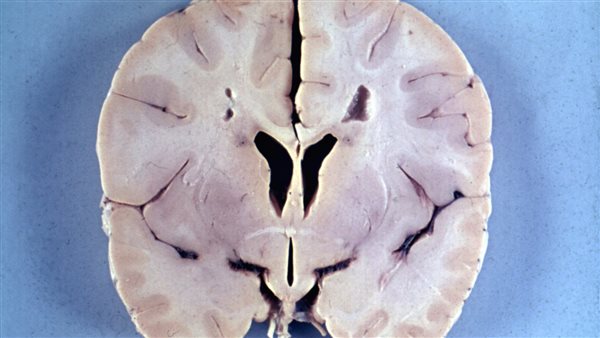

يُعد مرض الاسكندر أحد الأمراض النادرة وهو مرض يؤثر بشكل كبير على خلايا المخ والجهاز العصبي حيث يُعد من الأمراض المميتة ويسبب تأخر في النمو وبعض السمات الجسمانية، ويطلق عليه مسميات أخرى كثيرة مثل: حثل المادة البيضاء منزوع الأجنة، التنكس الليفي للخلايا النجمية.

يحدث اضطرابات في الجهاز العصبي وتسمى حثل المادة البيضاء وتؤدي إلى تدمير المايلين وهو العازل للألياف العصبية ويكون في صورة غطاء دهني ويقوم بتعزيز النقل السريع للنبضات العصبية، وإذا حدث أي خلل في المايلين فقد يتعطل انتقال النبضات العصبية، ويؤدي ذلك إلى إضعاف وظائف الجهاز العصبي.

• تضخم ملحوظ في حجم الدماغ والرأس.